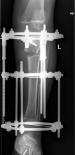

肢体短缩延长术,延长9厘米

术前 手术 术后功能恢复良好